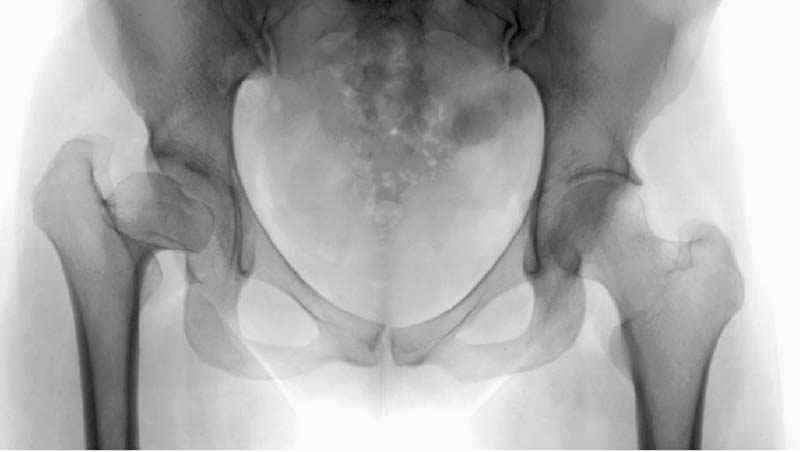

Рис.2 Та же трехмерная модель тазобедренного сустава без аналога связки головки бедра. Пружина динамометра удерживает тазовую часть модели от опрокидывания, поддерживая стабильность так же, как отводящие мышцы обеспечивают ее в отсутствии связки головки бедра.